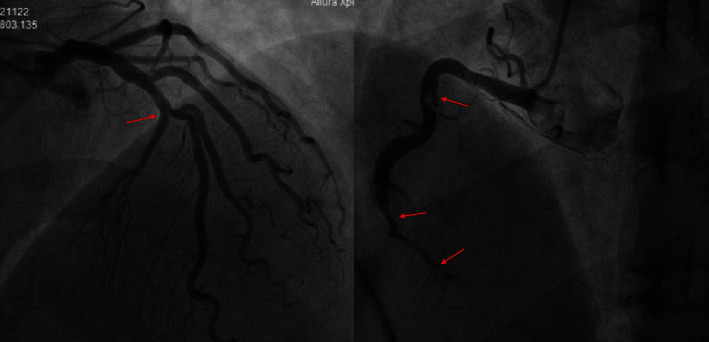

弗兰克征(Frank's sign,FS)是指耳廓和耳垂外缘之间的对角皮肤皱褶。FS已被确定为冠状动脉疾病(CAD)的一个独立变量。在临床研究中,FS 和既往心肌梗死的年轻患者仍鲜有报道。我们报告了一例 49 岁的男性吸烟者和糖尿病患者,他有心肌梗死病史,因 2 小时典型的心源性胸痛到急诊科就诊。他的急诊心电图(ECG)显示 ST 段抬高,入院后心脏生物标志物升高。体格检查中观察到对角线耳垂皱襞(DELC)。初步诊断为急性冠状动脉综合征(ACS)。随后,急性冠状动脉造影显示右冠状动脉(RCA)近端有裂缝样造影剂缺损,远段狭窄闭塞。患者立即接受了经皮冠状动脉介入治疗(PCI)。介入治疗后,患者的胸痛症状明显缓解。我们的病例表明,FS 作为常规心血管临床检查应得到高度重视,它可以毫不费力地应用于怀疑缺血性心脏病的筛查,并易于解释。这可以为年轻群体的初筛制定策略,并及时进行早期诊断和治疗。

Frank's sign (FS) refers to a diagonal skin fold between the tragus and the outer edge of the earlobe. FS has been identified as an independent variable in coronary artery disease (CAD). Young patients with FS and previous myocardial infarction are still rarely reported in clinical studies. We report the case of a 49-year-old male smoker and diabetic, with a history of myocardial infarction, who presented to the emergency department due to 2 h typical cardiac chest pain. His urgent electrocardiography (ECG) showed ST elevation, and cardiac biomarkers were elevated after admission. A diagonal earlobe crease (DELC) was observed in physical tests. The preliminary diagnosis considered acute coronary syndrome (ACS). Subsequently, acute coronary artery angiography demonstrated a slit-like contrast defect in the proximal right coronary artery (RCA), with stenosis and occlusion in the distal segment. The percutaneous coronary intervention (PCI) was performed immediately. The patient's chest pain symptoms were relieved significantly after intervention. Our case indicates that FS should be highly regarded as a routine cardiovascular clinical examination, which can be effortlessly applied and be easily interpreted for screening to suspect the presence of ischemic heart disease. This may set strategies for primary screening in a younger population and prompt early diagnosis and treatment.